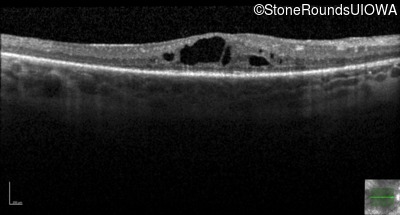

Optical Coherence Tomography - Right - 20/60 -1

Exemplar / OCT Stack